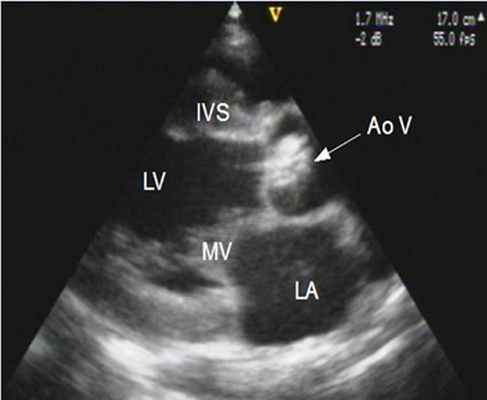

Двухмерная ЭхоКГ:

- Систолическая сепарация между передней (правой коронарной) створкой и задней (некоронарной) створкой меньше 1,5 см.

- Утолщенные аортальные створки в парастернальной проекции длинной оси левого желудочка или поперечном сечении на уровне магистральных сосудов (Этот феномен более отчетливо визуализируется в диастолу, причем правая коронарная створка повреждается значительно чаще, чем левая).

- Выгибание аортальных створок за линию смыкания (пролапс аортальных створок в выходной тракт левого желудочка)(рис.131).

4. Эхокардиография (УЗИ-сердца) - является основным методом диагностики и оценки прогноза больных с аортальным стенозом. При этом возможна визуализация структур корня аорты и выносящего тракта левого желудочка, оценка подвижности створок и их состояния, определение локализации стеноза.

- ЭхоКГ. ЭХОКГ позволяет определить: структуру клапана (двустворчатый клапан, утолщение створок, фиброз, кальциноз, вегетации), характер его движения (подвижность створок, степень открытия) и площадь отверстия; изменения корня аорты (постстенотическая дилатация), объем левого желудочка, выраженность гипертрофии левого желудочка, нарушения локальной сократимости левого желудочка (указывающие на ИБС), ФВ, объем левого предсердия, состояние других клапанов. Доплеровское исследование позволяет с высокой точностью определить градиент давления между аортой и левым желудочком.